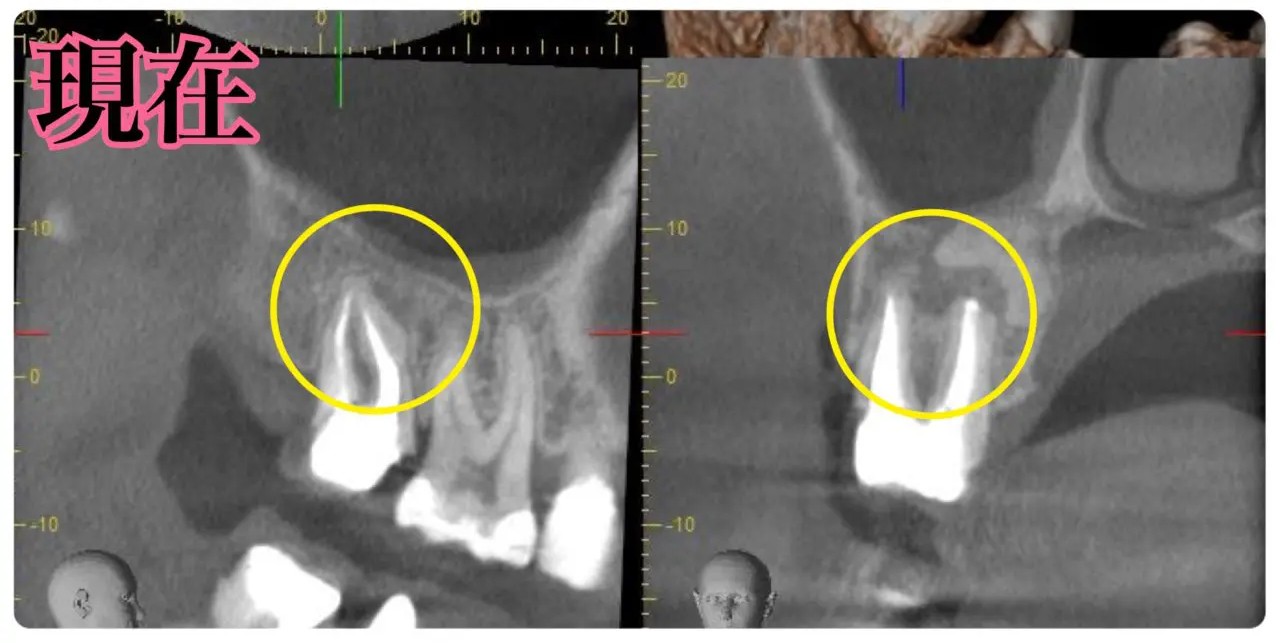

根尖病変によりCT上で黒く写っていた部分が白っぽくなっているのがわかりますか?

溶けていた部分の歯槽骨が回復しているということです!

また、上顎洞の肥厚は収まり、頬側の歯槽骨もくっきり映っています。予想以上に歯槽骨が回復しているので、今後外科的処置をしなくても良いのではないかと判断しました。大きなダメージがあった歯なので補綴物を入れた後も欠かさずに経過観察を行い、少しでも長くご自身の歯で生活して頂きたいと思います。